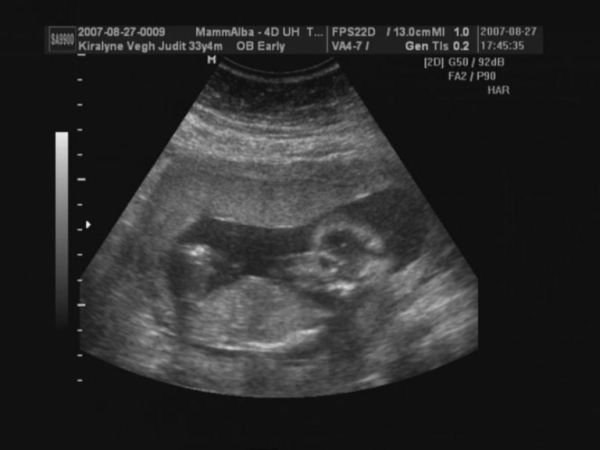

Judy, nagyon szép babátok van, gyerekek mit szóltak???